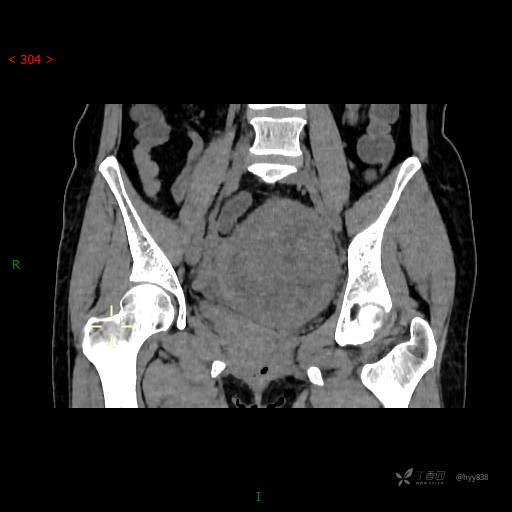

静脉期